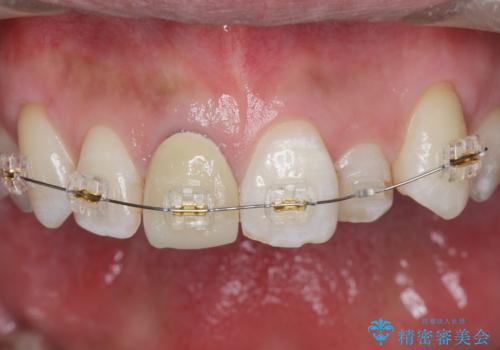

奥に引っ込んでいる前歯を並べたい 矯正治療とセラミック治療

- 奥に引っ込んでいる前歯を矯正治療で並べたい!色の気になる前歯のクラウンをやり替えたい!と希望され来院されました。

奥に位置している前歯を部分ワイヤー矯正ののちマウスピース矯正インビザラインで並べ、矯正治療後に審美的なジルコニアクラウンを作製していきます。